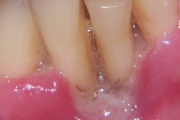

ANUG (äge nekrotiseeruv haavandiline gingiviit/parodontiit)